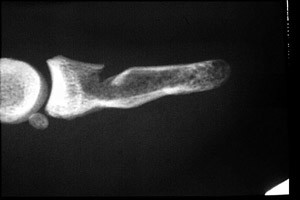

- Click on the image for a larger versionAAP radiograph of the first digit. This reveals a transverse fracture through the distal phalanx of digit one.